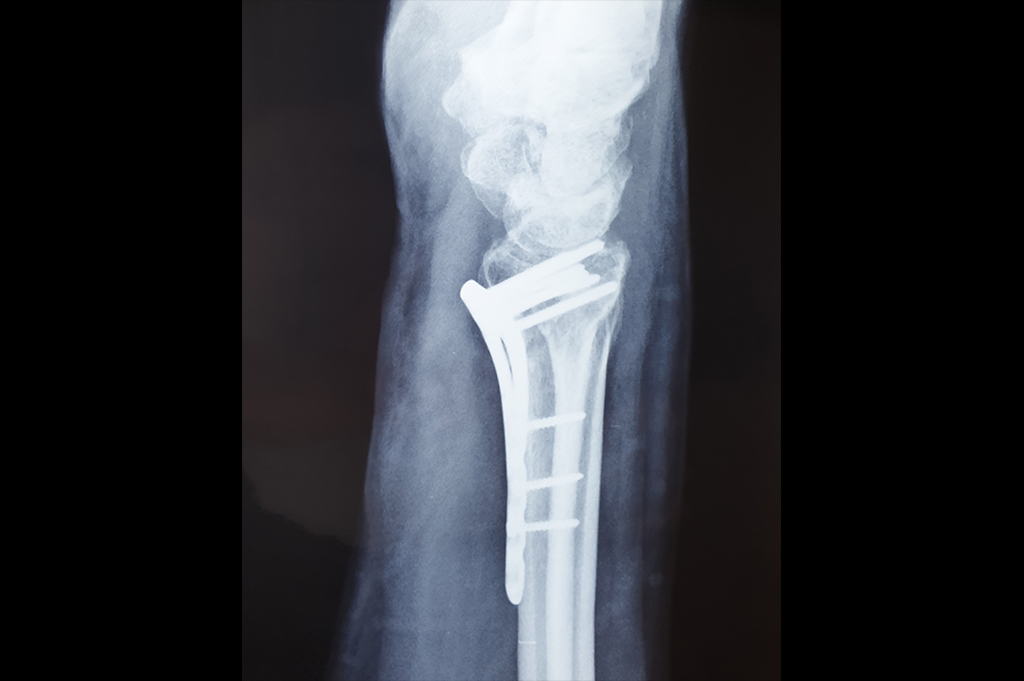

Proximal Tibia